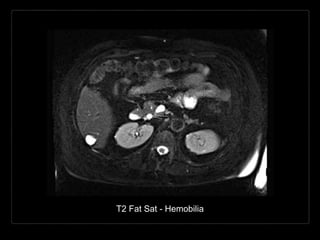

HEMOBILIA

Presencia de sangrado hacia el

árbol biliar y sangre en la bilis.

• Causas:

• trauma/biopsia

• enfermedad inflamatoria

• colelitiasis

• tumor

• anormalidades vasculares

Hallazgos por TC y RM

• contenido con densidad/intensidad hemática

• contenido heterogéneo de la vesícula biliar

• posición dependiente

• vesícula distendida con engrosamiento de su

pared

• + C

• reforzamiento de la pared vesicular

T2 Fat Sat - Hemobilia

HEMOBILIA Presencia de sangradohacia el árbol biliar y sangre en la bilis. • Causas: • trauma/biopsia • enfermedad inflamatoria • colelitiasis • tumor • anormalidades vasculares

Hallazgos por TCy RM • contenido con densidad/intensidad hemática • contenido heterogéneo de la vesícula biliar • posición dependiente • vesícula distendida con engrosamiento de su pared • + C • reforzamiento de la pared vesicular

T2 Fat Sat- Hemobilia

• #91 There is a change in common bile duct (CBD) internal intensity status post liver biopsy. Pre-biopsy MRI demonstrates normal internal hyperintensity of CBD. Post-biopsy demonstrates heterogenous low T2 and mild T1 in phase hyperintensity. The post contrast T1 fat sat image has internal mild hyperintense debris. Findings are consistent with hemobilia after recent liver biopsy.

• #92 There is a change in common bile duct (CBD) internal intensity status post liver biopsy. Pre-biopsy MRI demonstrates normal internal hyperintensity of CBD. Post-biopsy demonstrates heterogenous low T2 and mild T1 in phase hyperintensity. The post contrast T1 fat sat image has internal mild hyperintense debris. Findings are consistent with hemobilia after recent liver biopsy.